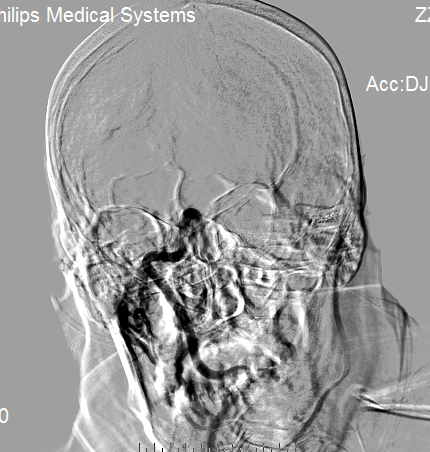

右侧颈内动脉造影显示右侧颈内动脉闭塞。

侧枝代偿差。

选择4.0×20mm支架,采用swim技术取栓2次,取出少量暗红色血栓,颈动脉造影未见血流恢复,单支架取栓无效。

考虑血栓负荷量大,遂采用双支架取栓技术。

该病例为颈内动脉C1段远端闭塞,血栓负荷率大,我们采用常规的SWIM技术(支架取栓+抽栓),但是效果不佳,于是改为双支架串联技术取栓,达到mTICI 2b级血管再通效果。